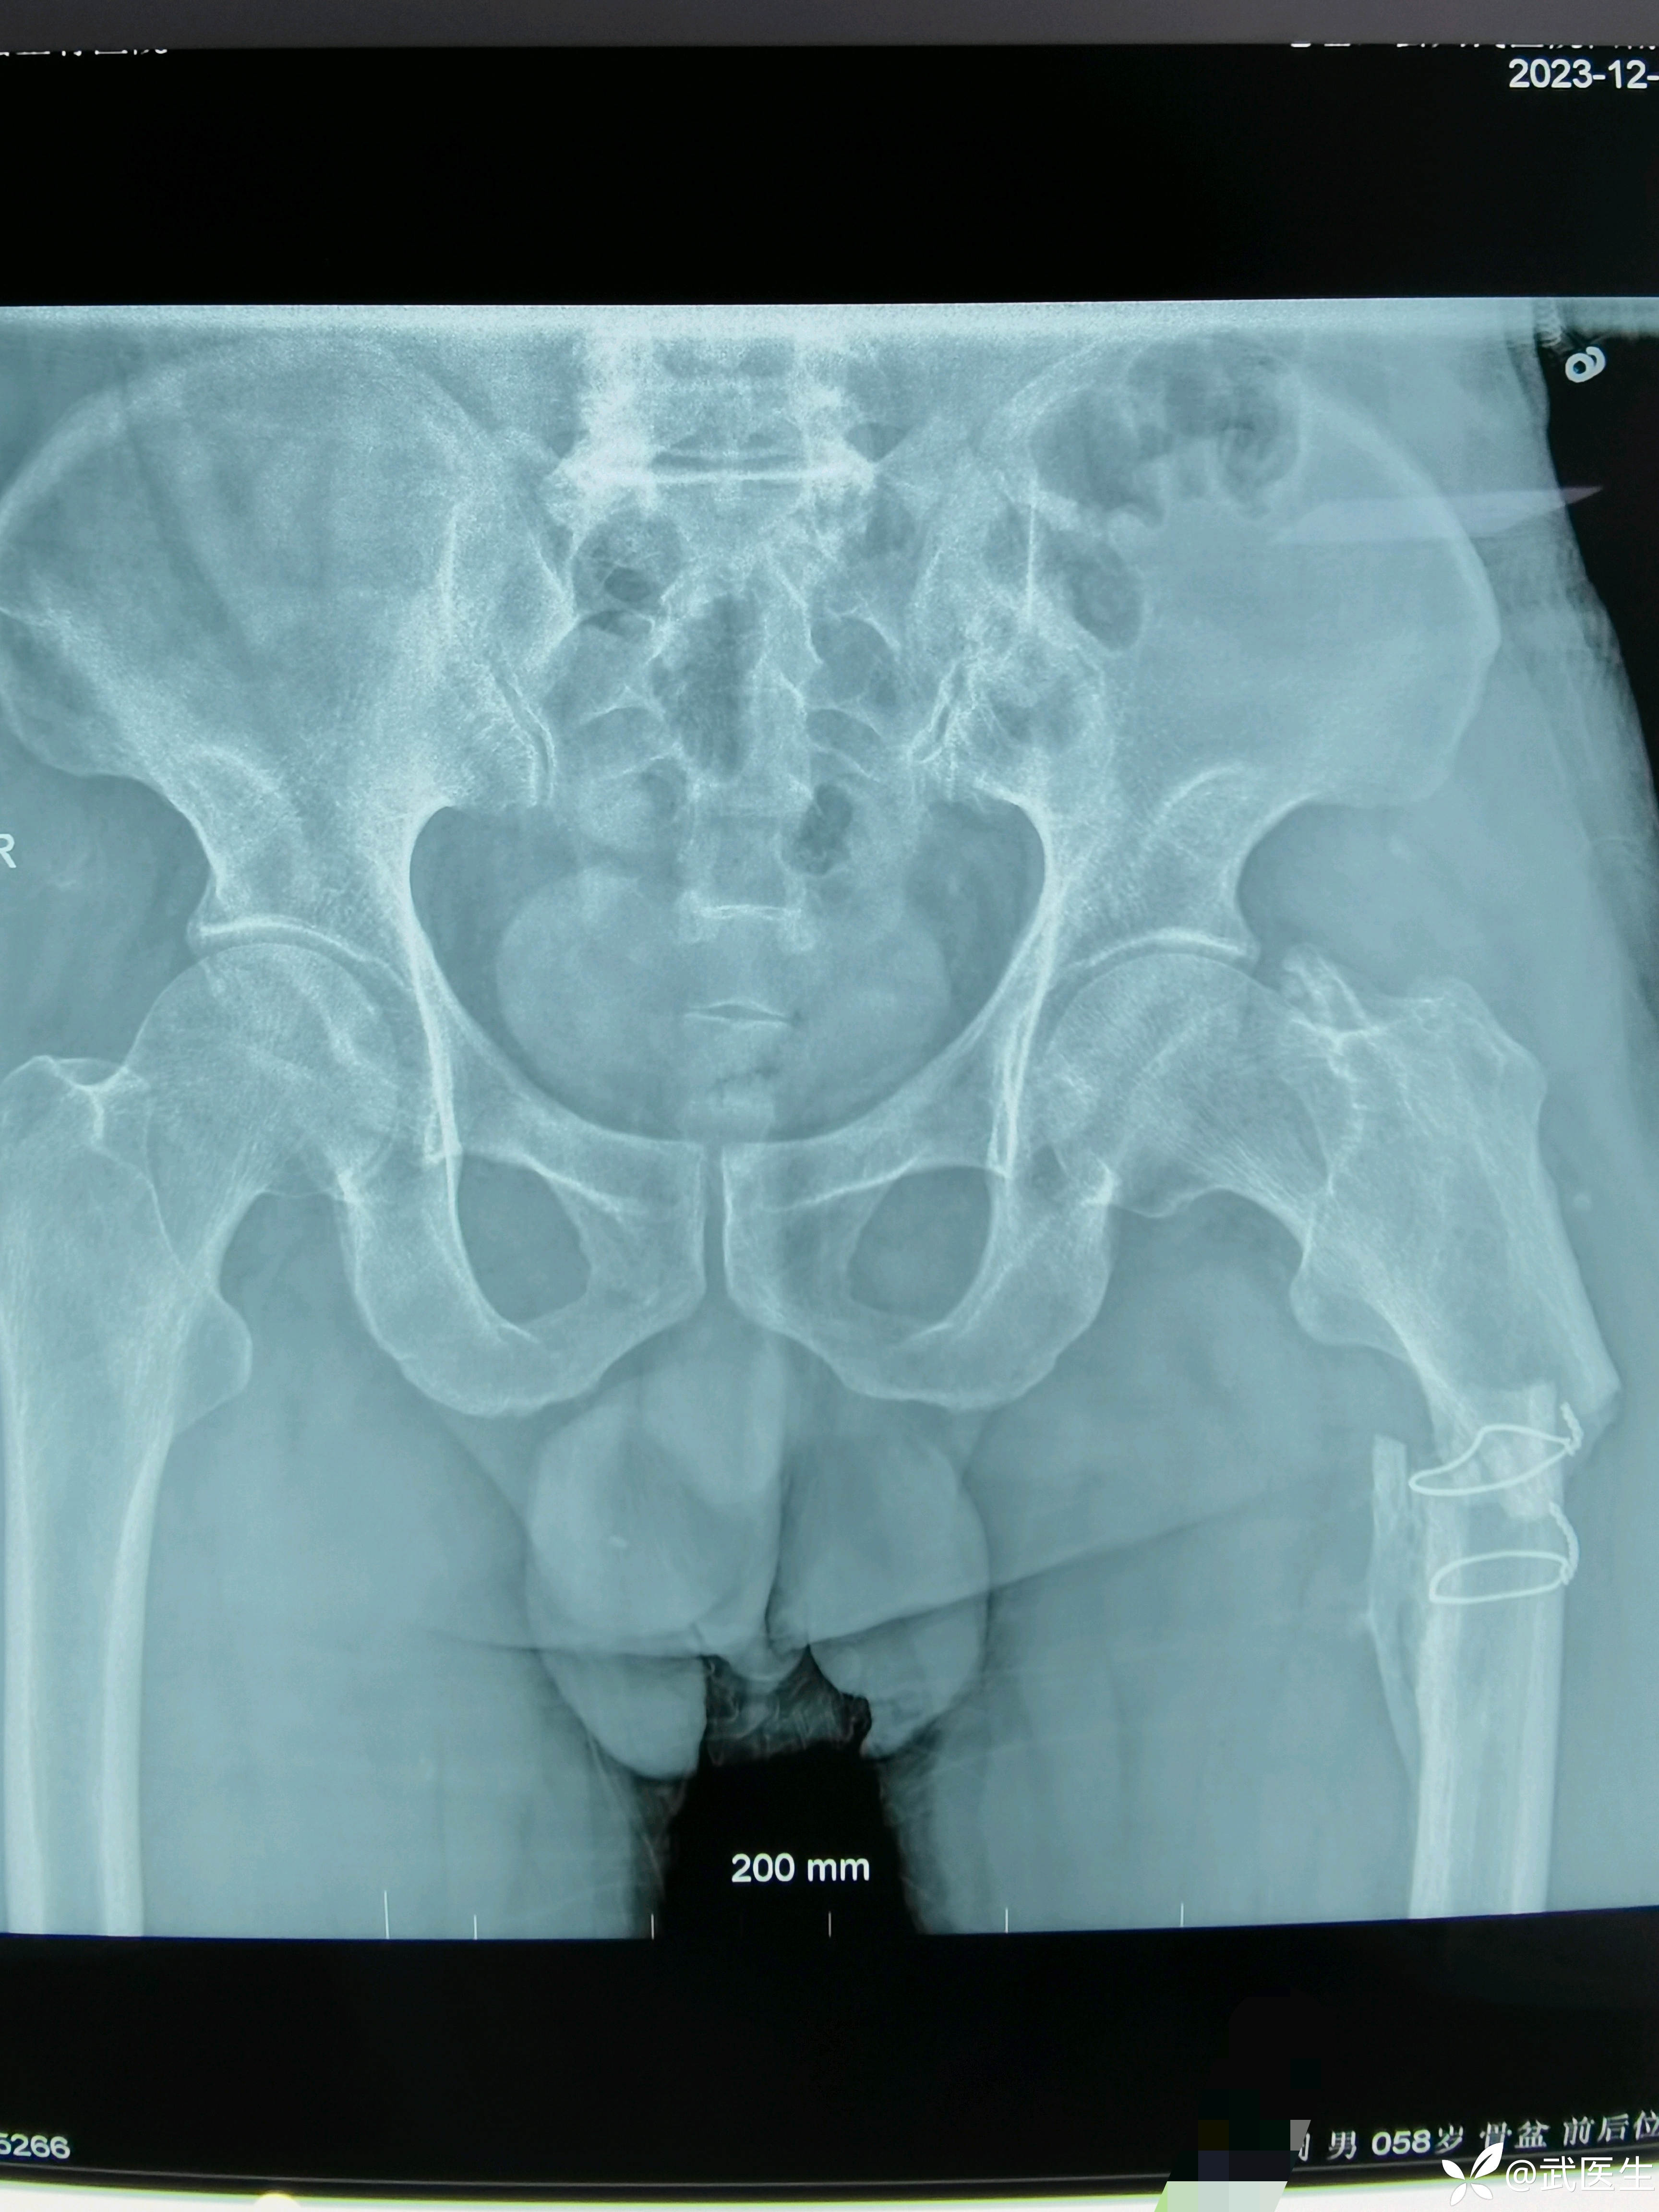

男,58岁,路滑摔倒致左髋疼痛活动受限一小时就诊,片子如下